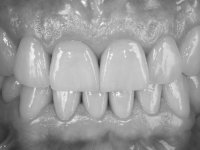

Avaliada a situação inicial em conjunto com o médico dentista, foi considerado prioritário alterar a forma dos dentes, subir 1.5mm a D.V.O. e descruzar a mordida do 1º Quadrante. Na confeção da ponte provisória superior de acrílico com reforço metálico foram já ensaiadas essas alterações. Optamos por um monobloco de 13 dentes com o intuito de manter a estabilidade posicional dos dentes re- preparados. Após remoção das coroas e pontes antigas foi feita a re-preparação dentária. A ponte provisória foi rebasada em boca, primeiro com acrílico auto-polimerizável e depois com resina composta. Após 4 semanas de integração da ponte provisória superior foi confecionada a ponte provisória inferior, corrigindo-se finalmente as discrepâncias existentes no plano oclusal. As impressões foram realizadas com a técnica de dupla mistura, com dupla mistura. Simultaneamente foram feitos os registos da relação inter-maxilar e da relação do maxilar superior com a base do crânio, utilizando o arco facial. Montados os modelos de trabalho em articulador semi-ajustável, foram confecionadas as peças próteticas, utilizando tecnologia CAD-CAM para a realização das infra-estruturas em zircónia. A colocação da cerâmica foi feita procurando que a forma dos dentes reproduzisse uma forma anatómica natural. A tonalidade foi condicionada pela vontade do paciente. Foi feita uma prova com a cerâmica em “biscuit” para verificação técnica e validação estética. Após aprovação pelo paciente o trabalho foi finalizado e colocado em boca.